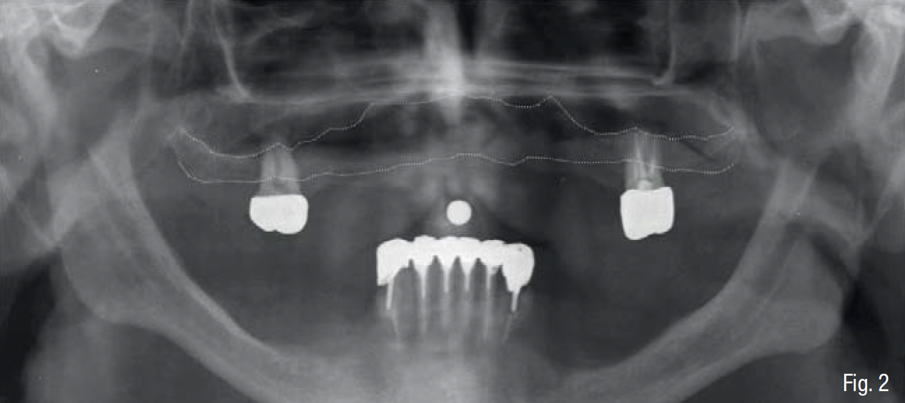

Gli esami radiologici di primo livello, quali la OPT, evidenziavano un’altezza ossea sufficiente al posizionamento implantare, ma la successiva analisi di secondo livello, quale la CBCT, evidenziava la presenza di una grave atrofia orizzontale a livello della regione edentula che rendeva impossibile la chirurgia implantare, oltre ad un quadro di sinusite mascellare cronica bilaterale. Su richiesta del paziente, si è deciso di mantenere i 2 molari sup. che sono stati trattati endodonticamente e successivamente protesizzati con 2 corone in zirconia; e di non eseguire il rialzo di seno mascellare bilaterale evitando l’iter terapeutico di approfondimento ORL.

In accordo con il paziente si decide di eseguire un intervento di rigenerazione ossea guidata (GBR) mediante una griglia in titanio customizzata e membrane riassorbibili (Figg. 2-4). Pertanto, 1 mese prima della chirurgia, è stato creato un modello osseo virtuale in formato .stl del mascellare sup. tramite segmentazione, a partire dai file .dicom della CBCT, utilizzando un software biomedicale dedicato (BTK- 3D, Biotec Srl, Dueville, Vicenza, Italy); è stato quindi eseguita la progettazione virtuale dell’aumento di volume osseo necessario per inserire gli impianti e la successiva progettazione della griglia customizzata al di sopra del volume aumentato; infine, è stata realizzata la griglia in titanio vera e propria mediante tecnologia di stampa 3D basata su sinterizzazione laser del titanio (3D-Mesh BTK, Biotec Srl, Dueville, Vicenza, Italy) (Figg. 5-8).